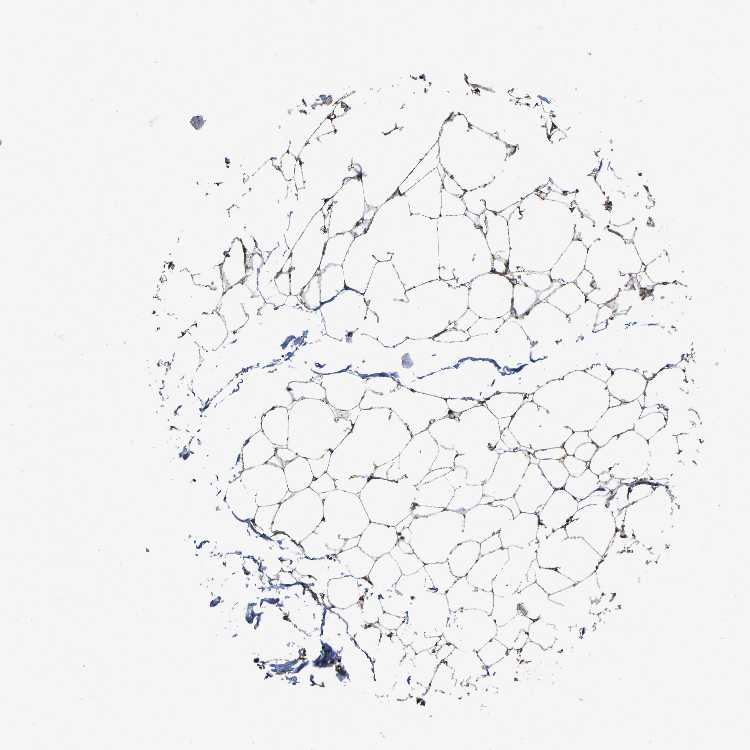

TISSUE PRIMARY DATA SOFT TISSUE Show tissue menu

SOFT TISSUE - Expression summary

SOFT TISSUE 1 - Antibody stainingi

Antibody staining in the annotated cell types in the current human tissue is reported as not detected, low, medium, or high, based on conventional immunohistochemistry profiling in selected tissues. This score is based on the combination of the staining intensity and fraction of stained cells.

Each image is clickable and will lead to virtual microscopy that enables deeper exploration of all samples and also displays staining intensity scores, fraction scores and subcellular localization as well as patient and tissue information for each sample.

Antibody HPA017882

Chondrocytes High

Fibroblasts High